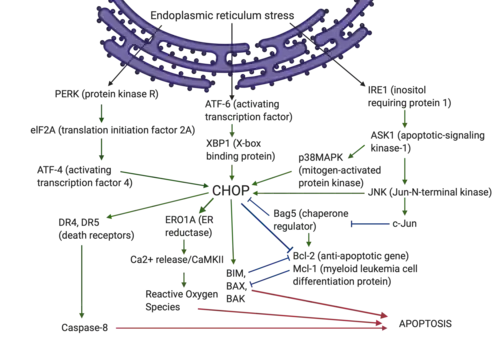

Due to a variety of upstream and downstream regulatory interactions, CHOP plays an important role in ER stress-induced apoptosis caused by a variety of stimuli such as pathogenic microbial or viral infections, amino acid starvation, mitochondrial stress, neurological diseases, and neoplastic diseases.

Under normal physiological conditions, CHOP is ubiquitously present at very low levels.[9] However, under overwhelming ER stress conditions, the expression of CHOP rises sharply along with the activation of apoptotic pathways in a wide variety of cells.[8] Those processes are mainly regulated by three factors: protein kinase RNA-like endoplasmic reticulum kinase (PERK), activating transcription factor 6 (ATF6), and inositol requiring protein 1 (IRE1α) [10][11]

During ER stress, CHOP is mainly induced via activation of the integrated stress response pathways through the subsequent downstream phosphorylation of a translation initiation factor, eukaryotic initiation factor 2α (eIF2α), and induction of a transcription factor, activation transcription factor 4 (ATF4),[12] which converges on the promoters of target genes, including CHOP.

Under ER stress, activated transmembrane protein ATF6 translocates to the nucleus and interacts with ATF/cAMP response elements and ER stress-response elements,[17] binding the promoters and inducing transcription of several genes involved in unfolded protein response (including CHOP, XBP1 and others).[18][19] Thus, ATF6 activates the transcription of both CHOP and XBP-1, while XBP-1 can also upregulate the expression of CHOP.[20]

ER stress also stimulates transmembrane protein IRE1α activity.[21] Upon activation, IRE1α splices the XBP-1 mRNA introns to produce a mature and active XBP-1 protein,[22] that upregulates CHOP expression[23][24][25] IRE1α also stimulates the activation of the apoptotic-signaling kinase-1 (ASK1), which then activates the downstream kinases, Jun-N-terminal kinase (JNK) and p38 mitogen-activated protein kinase (p38 MAPK),[26] which participate in apoptosis induction along with CHOP.[27] The P38 MAP kinase family phosphorylates Ser78 and Ser81 of CHOP, which induces cell apoptosis.[28] Moreover, research studies found that the JNK inhibitors can suppress CHOP upregulation, indicating that JNK activation is also involved in the modulation of CHOP levels.[29]

As a transcription factor, CHOP can regulate the expression of many anti-apoptotic and pro-apoptotic genes, including genes encoding the BCL2-family proteins, GADD34 and TRB-3.[30][31] In the CHOP-induced apoptotic pathway, CHOP regulates the expression of BCL2 protein family, that includes anti-apoptotic proteins (BCL2, BCL-XL, MCL-1, and BCL-W) and pro-apoptotic proteins (BAK, BAX, BOK, BIM, PUMA and others).[32][33]

Under ER stress, CHOP can function as either a transcriptional activator or repressor. It forms heterodimers with other C/EBP family transcription factors via bZIP-domain interactions to inhibit the expression of genes responsive to C/EBP family transcription factors, while enhancing the expression of other genes containing a specific 12–14 bp DNA cis-acting element.[34] CHOP can downregulate the expressions of anti-apoptotic BCL2 proteins, and upregulate the expression of proapoptotic proteins (BIM, BAK and BAX expression).[35][36] BAX-BAK oligomerization causes cytochrome c and apoptosis-inducing factor (AIF) release from mitochondria, eventually causing cell death.[37]

Death receptor-mediated apoptosis occurs via activation of death ligands (Fas, TNF, and TRAIL) and death receptors. Upon activation, the receptor protein, Fas-associated death domain protein, forms a death-inducing signaling complex, which activates the downstream caspase cascade to induce apoptosis.[44]

The PERK-ATF4-CHOP pathway can induce apoptosis by binding to the death receptors and upregulating the expression of death receptor 4 (DR4) and DR5. CHOP also interacts with the phosphorylated transcription factor JUN to form a complex that binds to the promoter region of DR4 in lung cancer cells.[44] The N-terminal domain of CHOP interacts with phosphorylated JUN to form a complex that regulates the expression of DR4 and DR5.[44] CHOP also upregulates the expression of DR5 by binding to the 5′-region of the DR5 gene.[45]

Under prolonged ER stress conditions, activation of the PERK-CHOP pathway will permit DR5 protein levels to rise, which accelerates the formation of the death-inducing signaling complex (DISC) and activates caspase-8,[46] leading to apoptosis[47]

In addition, CHOP also mediates apoptosis through increasing the expression of the ERO1α (ER reductase)[10] gene, which catalyzes the production of H2O2 in the ER. The highly oxidized state of the ER results in H2O2 leakage into the cytoplasm, inducing the production of reactive oxygen species (ROS) and a series of apoptotic and inflammatory reactions.[10][48][49][50]

Under most conditions, CHOP can directly bind to the promoters of downstream related genes. However, under specific conditions, CHOP can cooperate with other transcription factors to affect apoptosis. Recent studies have shown that Bcl-2-associated athanogene 5 (Bag5) is over-expressed in prostate cancer and inhibits ER stress-induced apoptosis. Overexpression of Bag5 results in decreased CHOP and BAX expression, and increased Bcl-2 gene expression.[52] Bag5 overexpression inhibited ER stress-induced apoptosis in the unfolded protein response by suppressing PERK-eIF2-ATF4 and enhancing the IRE1-Xbp1 activity.[53]